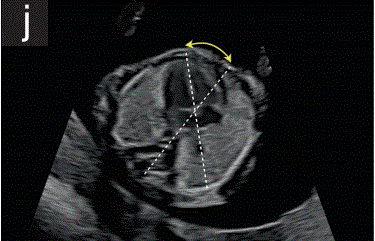

6.1在胎儿四腔平面上评估胸腔、肺和心脏(图2j),在此平面中,评估肋骨、肺、胸部和心脏位置,心脏轴指向左侧(正常轴位于30-60◦)肺部应呈现均匀回声,且应无胸腔积液。

胎儿mt是什么检查什么疼吗【文献学习/规范指南】ISUOG实践指南(2023更新): 11-14周胎儿超声检查(全文)_https://www.jmylbn.com_新闻资讯_第17张

2 11+0至14+0周时,可作为详细胎儿超声检查的一部分获得的解剖图。

(j)胎儿胸腔在心脏四腔切面水平的横断切面,显示胎儿肺、胸腔和胸主动脉及心脏的胸内位置。注意正常的心脏轴(虚线和黄色箭头)和心房和心室的相对对称性。